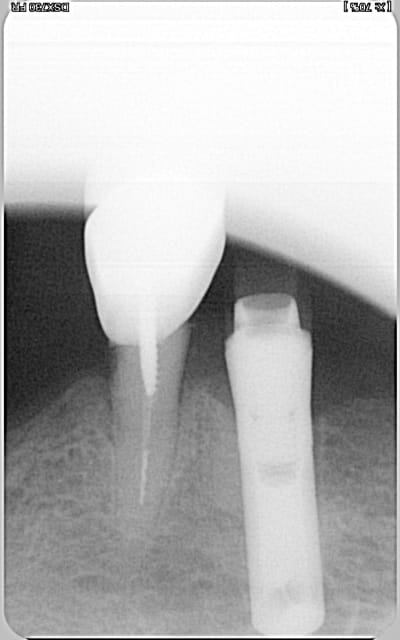

à mon tour, j'ai deux implants :

l'un semble être un branemark mais le deuxième...

anthofit de chez Anthogyr

http://whatimplantisthat.com/implant/anthofit-oi-straight-3/